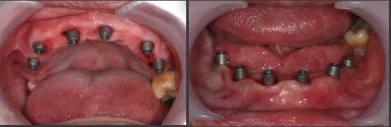

下颌即刻种植即刻修复手术过程

· 下颌士卓曼360数字化序列导板+预成临时修复体

· 翻瓣,利用松牙固定后的余留牙支持连接在一起的牙支持导板和基部导板,使骨支持的基部导板就位于骨面。

· 并用固位钉固定,拆除牙支持式导板,拔除余留牙。

· 基部导板上缘做为截骨线,精确去骨,平整骨面。

· 全程植入导板就位于基部导板上,固位钉固定,引导种植体植入。

· 种植体植入后,安装复合基台基底

· 临时修复体就位于基部导板,固位钉固定,口内Pick-up后取下修改,戴回口内,咬合关系良好。

上颌即刻种植即刻修复手术过程

· 上颌360数字化序列导板+预成临时修复体

· 拔除部分牙齿,翻瓣,利用剩余牙齿支持组合导板,辅助基部导板就位固定,基部导板上缘做为去骨线,精确去骨。

· 全程导板就位,引导种植体植入,安装复合基台。

· 种植体植入位置偏腭侧,唇侧骨量过于丰满,上颌骨前突,去骨修整骨边缘。

· 口内pick-up 固定临时修复体,患者上下颌咬合关系良好。

· 术后CBCT检查可见种植体植入位置佳,与术前设计一致。